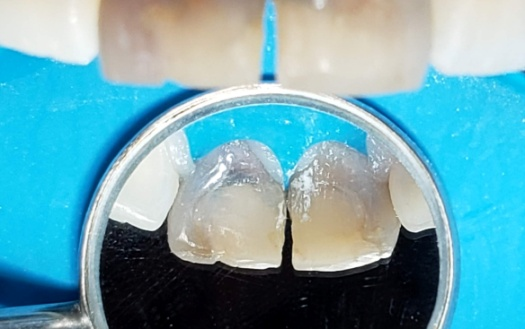

Fig. 2 Foto inicial vest y palatina

Paciente femenina de 28 años acude a la Facultad de odontología por motivo estético y molestia en el sector anterior y es derivada la asignatura Endodoncia B. Refiere alteración en la coloración de sus incisivos superiores y vergüenza al sonreír y molestia al morder con sus dientes delanteros. Al examen clínico, se observa restauración defectuosa y coronas manchadas (Fig 1-2). La paciente relata una caída hace más de 10 años, tras la cual le realizaron una reparación dental con tornillos metálicos.